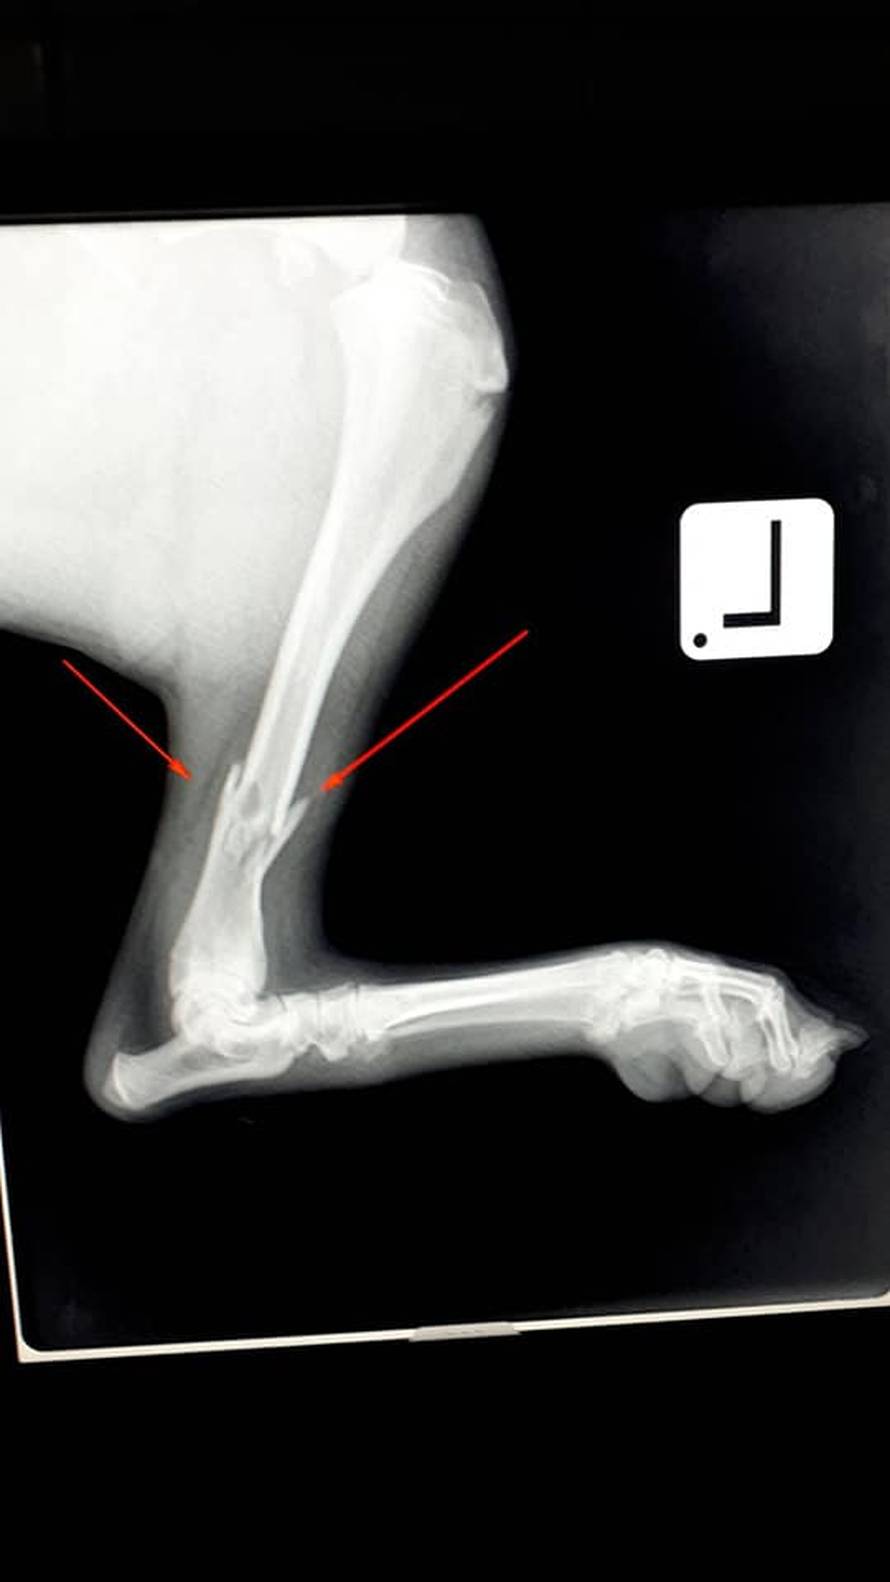

Vozač traktora iz mjesta Rašljeva iz BiH namjerno je nekoliko puta pregazio ženku haskija. Potom ju je odnio i zaključao na svom imanju. Pas je spašen i oporavlja se